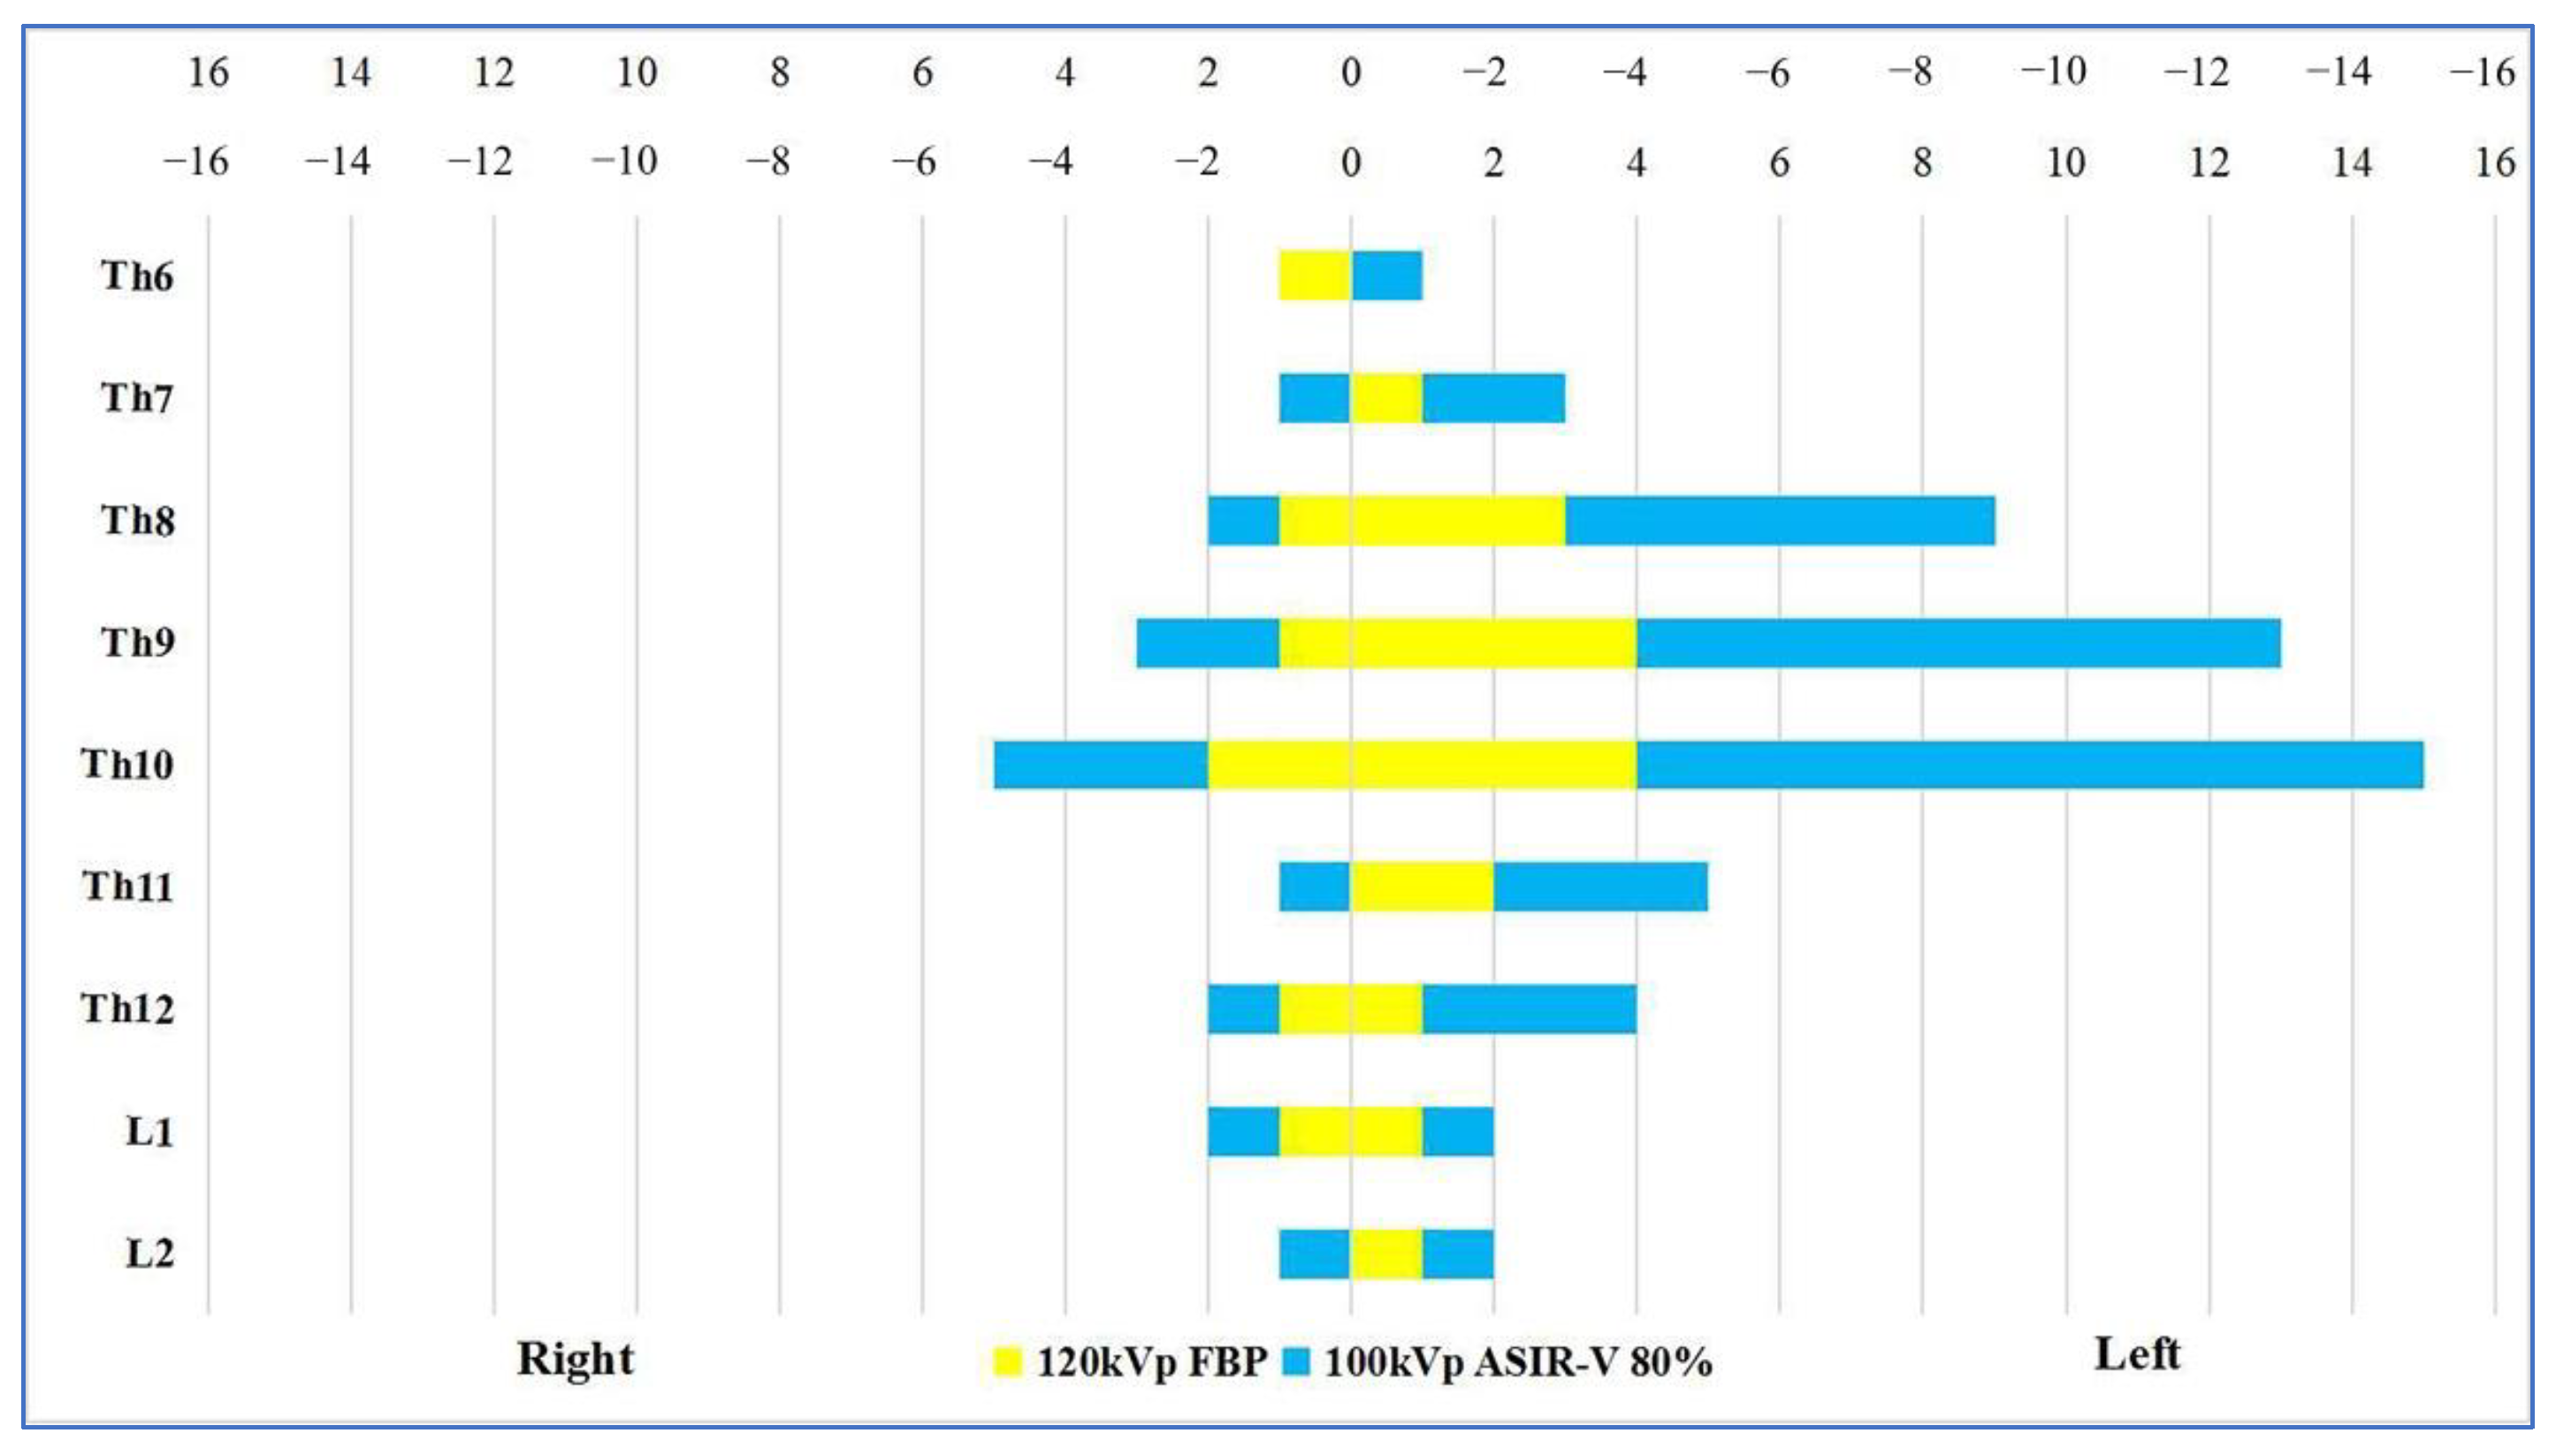

3.4. Visual Analysis of the AKA

3.5. Comprehensive Assessment